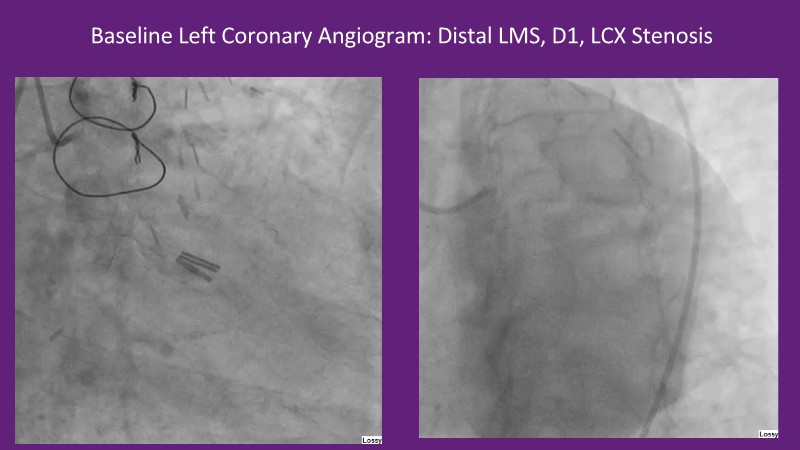

This EuroPCR 2025 session provides a comprehensive overview of drug-eluting balloons (DEBs) and their growing role in percutaneous coronary intervention (PCI). Gain a clear understanding of the clinical evidence and rationale supporting DEBs, including how these devices minimize metal implantation and effectively treat both standard and complex coronary lesions. The session highlights the mechanistic advantages of drug selection and sustained drug release technologies, with a focus on the SELUTION SLR DEB. Clinical updates include the LOVE-DEB study advocating a DEB-first approach in large vessel coronary artery disease, real-world performance data from the Malaysian registry, and practical case examples illustrating the transition to DEB-based PCI in clinical practice.